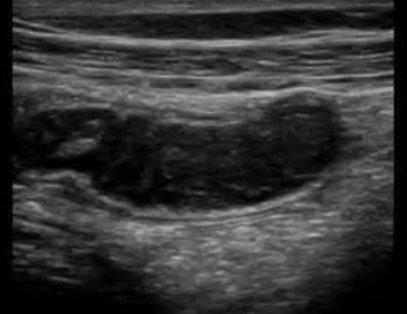

Mucocele